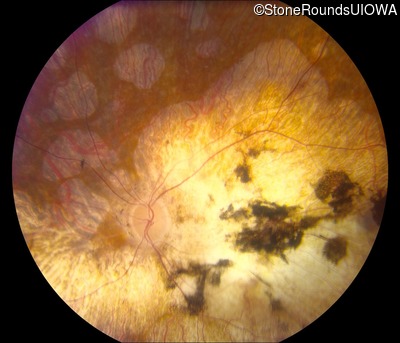

Fundus Photography - Right - Light Perception

Exemplar